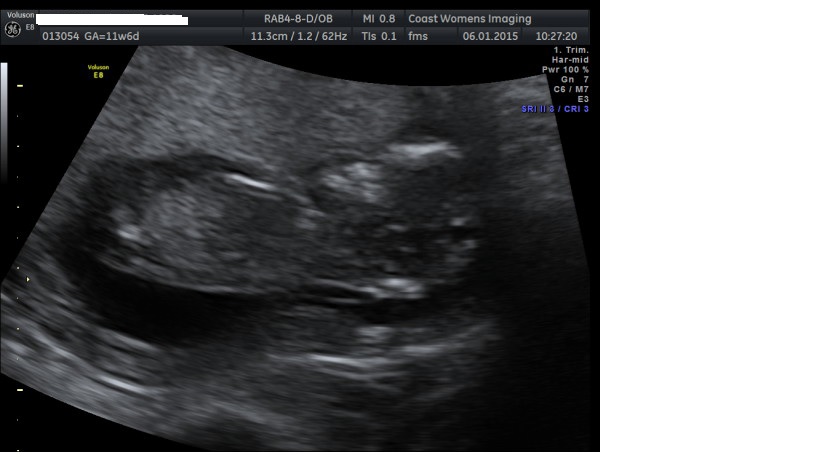

Just wondering if anyone has a guess on my scan pics, the technician made me feel stupid when I asked her about the nub theory and if she was familiar with it, so I didn't ask for a clear shot. I cant make anything out..